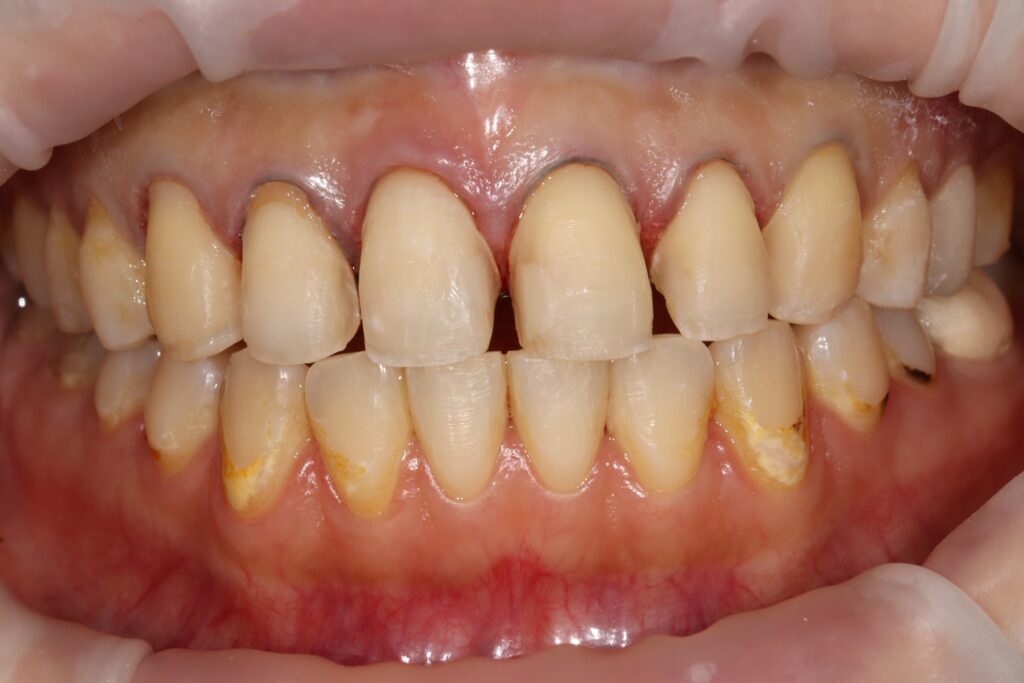

환자분께서는 교정치료 후

심미적 불만족으로 인해 광화문역치과인

본원에 내원해 주셨는데요.

치아 색상 불균형과 심미적 불만족을

주소로 구강 내 검진 결과,

상악 전치부에는 눈에 띄는 착색과 함께

치경부 우식이 다수 관찰되었으며,

일부 치아에서는 구조적인 손상까지

동반된 상태였습니다.